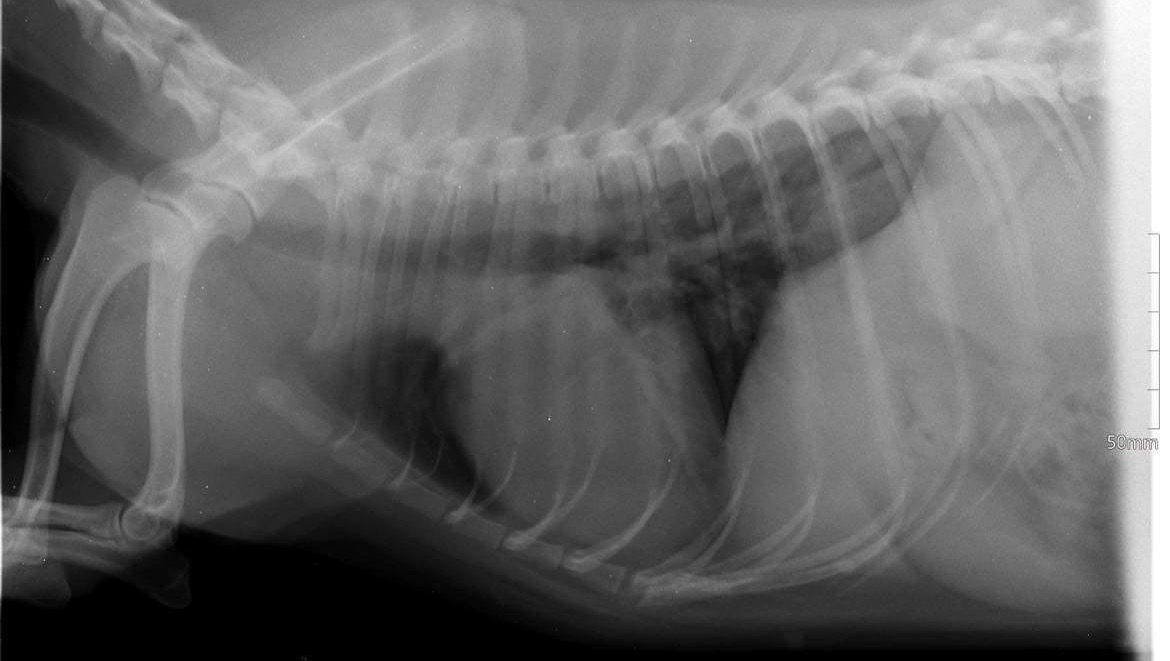

Two weeks ago, she was acting very odd. We took her to a vet and we were under the impression that she was depressed over the new puppy we adopted, (Ricky) but over time we noticed that she stopped pooping, so we took her to the vet again, and today ( 20.01.22.)we found out ,she has a lump in her right kidney. We don’t know yet if it’s cancer or not, we need to do further analysis but no matter what ,she needs the surgery! We have limited time and it’s heartbreaking, we would appreciate all the help and love you can give Pele in the times of need !…..